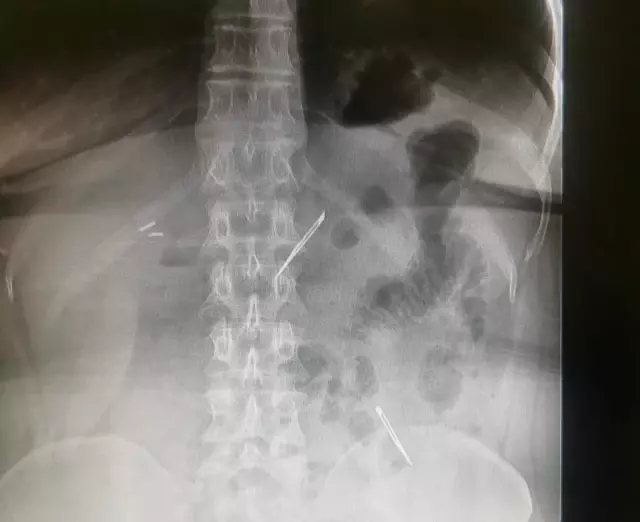

Sağlık Bilimleri Üniversitesi Ankara Atatürk Sanatoryum Eğitim ve Araştırma Hastanesi'ne mide ve karın bölgesinde aşırı ağrı şikayeti ile müracaat eden 46 yaşındaki D.E.'nin yapılan tahlil, tetkik ve çeşitli görüntülemelerden sonra bağırsak kısmında 2 adet neşter olduğu tespit edildi. Genel cerrahi kliniği tarafından zorlu bir ameliyat sonrasında neşterler kadının vücudundan çıkarıldı. 46 yaşındaki D.E. neşterleri nasıl yuttuğunu bilmediğini tahminen ekmek ile birlikte yutabilmiş olabileceğini ifade etti. Ameliyatı gerçekleştiren Sağlık Bilimleri Üniversitesi Ankara Atatürk Sanatoryum Eğitim ve Araştırma Hastanesi Genel Cerrahi Kliniği Eğitim ve İdari sorumlusu Prof. Dr. Hakan Buluş ise hastanın yoğun şikayetleri üzerine çektikleri röntgen sonrasında 2 adet neşteri görünce şaşkına uğradıklarını söyledi.

Hastanın şikayetlerinin artması üzerine gerçekleştirilen tetkiklerde 46 yaşındaki kadının karın bölgesinde 2 adet yabancı cisim olduğunu tespit ettiklerini, detaylı inceleme sonucunda bu cisimlerin neşter olduğunu fark ettiklerini belirten Prof. Dr. Buluş, "Yaklaşık 10 gün önce kliniğimize karın ağrısı ve bulantı şikayetleri ile başvurdu. Bizim yaptığımız fiziki muayene ve tetkiklerinde hastanın direkt karın grafisinde 2 adet yabancı cisim olduğunu tespit ettik. Aslında yabancı cisim bizim güncel grafiğimizde sık karşılaştığımız bir durum değil, fakat nadir de olsa görebildiğimiz bir patoloji.

Biz de bunun üzerine ayrıntılı değerlendirmeler ve tetkikler yaptık. Sonrasında 2 adet yabancı cismin bistüri (neşter) ile uyumlu olduğunu gördük. Bunun üzerine hastanın şikayetlerinin de artması üzerine, ameliyat kararı verdik. Yaptığımız ameliyatta ince bağırsağın yaklaşık 180'inci santimetresinde bu yabancı cisimlerin olduğunu tespit ettik. Bunun üzerine ameliyatla bunları çıkarttık. Hastamızın sağlık durumu şuan gayet iyi. Ameliyattan sonraki üçüncü günü. Şuan bir problemi yok, inşallah birkaç gün içerisinde şifa ile taburcu etmeyi düşünüyoruz" şeklinde konuştu.

Çıkardıkları cismin, neşterin normalde ameliyatlarda kullanılan bir malzeme olduğunu söyleyen Prof. Dr. Buluş, "Çıkardığımız yabancı cisimler bizim ameliyatlarda sıkça kullandığımız 11 numara dediğimiz bir bistüri tipi. Ebatları da yaklaşık 4 santime yarım santim ebatlarında. Ucunun sivri olması nedeniyle ince bağırsak mukozasına saplanarak enflamasyon ve bir karın ağrısı yapması, sonrasında da ağrı şikayetlerinin artmasına neden olmasından dolayı ameliyat kararı verdik" diye konuştu.